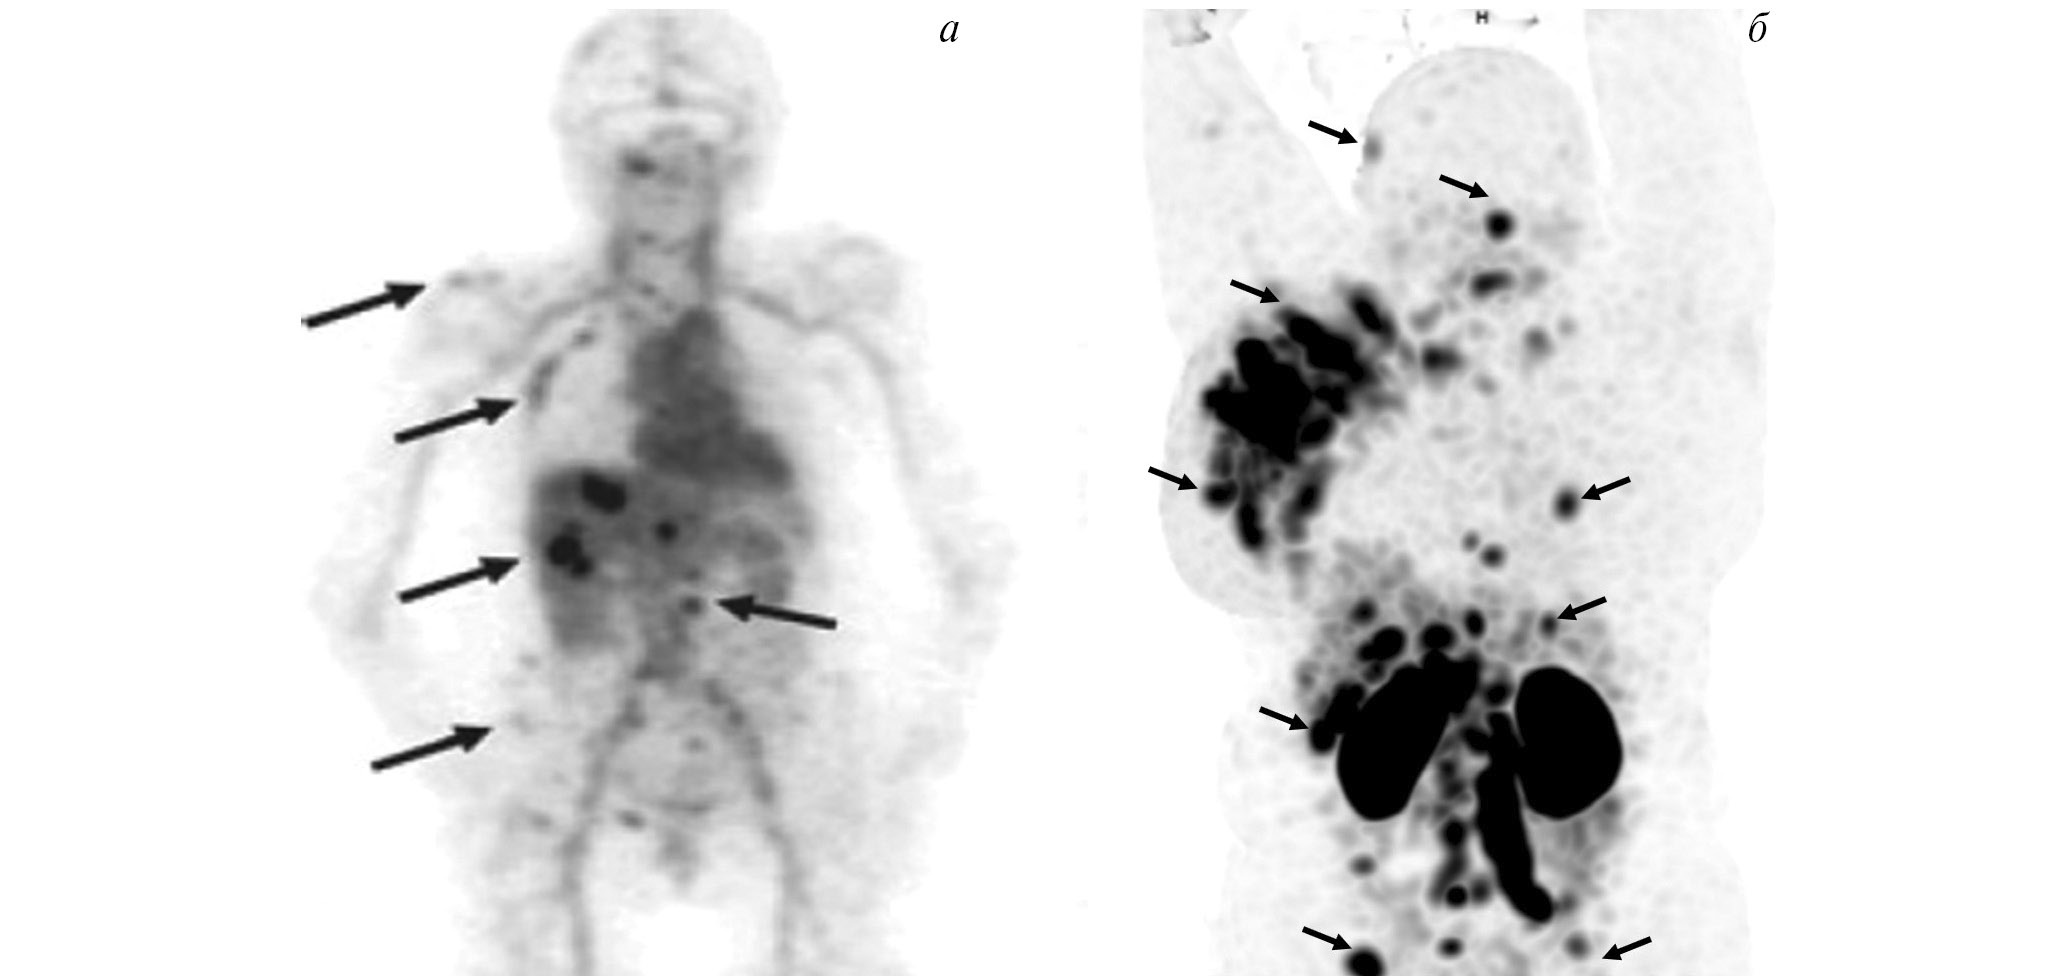

Изотопы таллия (201Tl и 199Tl) выступают биологическими аналогами К+, проникают внутрь клетки с помощью Na-K-ATФ-зависимой помпы и локализуются преимущественно в митохондриях. Эти радиофармпрепараты активно аккумулируются в тканях с интенсивным энергетическим обменом (к числу которых можно смело отнести злокачественные клетки) и способны участвовать в диагностике самых разнообразных опухолей, включая рак молочной железы, гортани и гортаноглотки (рис. 6) [38]. Кроме того, нуклиды таллия могут использоваться для динамической оценки противоопухолевой терапии [39]. Разработанный в ТПУ и Томском НИМЦ 199Tl выгодно отличается от своего известного аналога 201Tl коротким периодом полураспада (7.4 и 72 ч соответственно) и более низкой дозовой нагрузкой в процессе диагностической процедуры.

Рис. 6. ОФЭКТ с 199Тl пациента с раком молочной железы Стрелками обозначено накопление РФЛП в опухоли

Радиофармпрепарат 99mTc-1-Тио-D-глюкоза и набор для его приготовления разработаны в НИИ онкологии Томского НИМЦ и ТПУ (“Тиоскан, 99mТс”, Россия). Неповреждённый гематоэнцефалический барьер непроницаем для данного препарата, поэтому 99mTc-1-Тио-D-глюкоза хорошо показала себя в диагностике опухолей головного мозга (рис. 7) [43]. Кроме того, ОФЭКТ/КТ с 99mTc-1-Тио-D-глюкозой рекомендована для стадирования и прогноза результатов лечения лимфопролиферативных заболеваний (рис. 8) [44, 45].

Рис. 7. ОФЭКТ/КТ с 99mTc-1-Тио-D-глюкозой пациента с рецидивом глиобластомы. Стрелками обозначено накопление РФЛП в опухоли

Рис. 8. ОФЭКТ/КТ с 99mTc-1-Тио-D-глюкозой пациентки с лимфомой Ходжкина. Стрелками обозначено накопление РФЛП в лимфатических узлах правой аксиллярной области